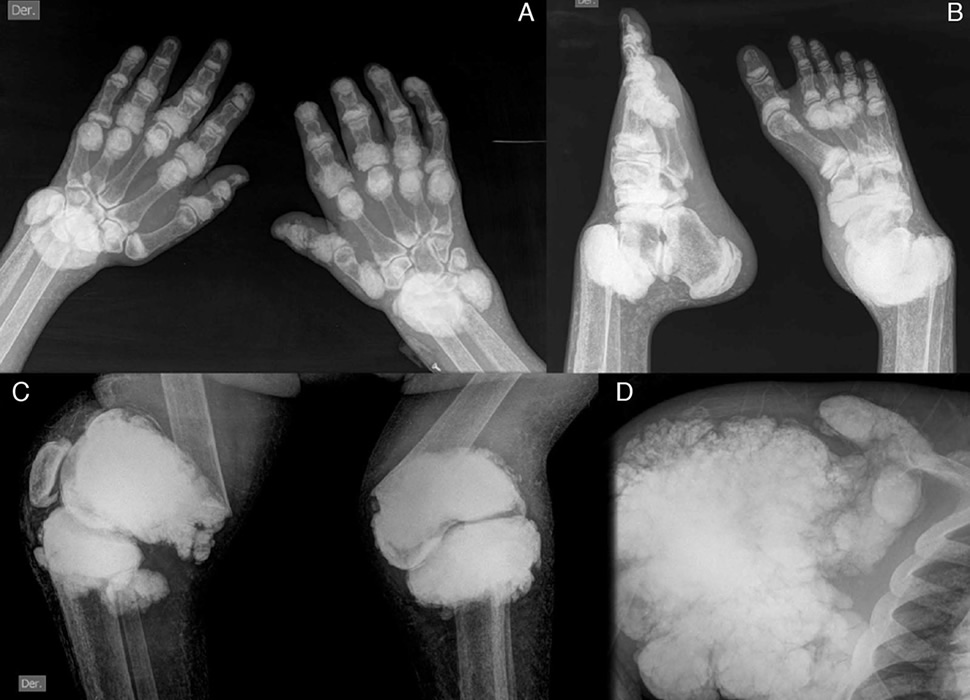

Ревматоидный артрит стопы: рентгеновские снимки и стадии заболевания

Раздел: Визуальный дайджест